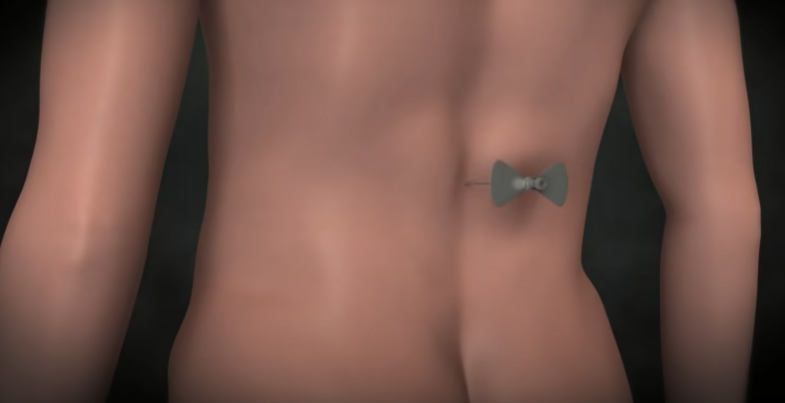

뇌척수액 누출 두통의 치료

시술은 국소 마취제를 주사한 후에, 가느다란 관인 카테터를 척수를 싸고 있는 격막의 바깥 공간에 삽입하고

그 안으로 환자의 혈액을 주입하면 피가 응고되면서 누수를 막아 준다.

이때 새로 만들어진 뇌척수액이 채워지면서 주저앉았던 뇌가 제자리를 찾아간다.